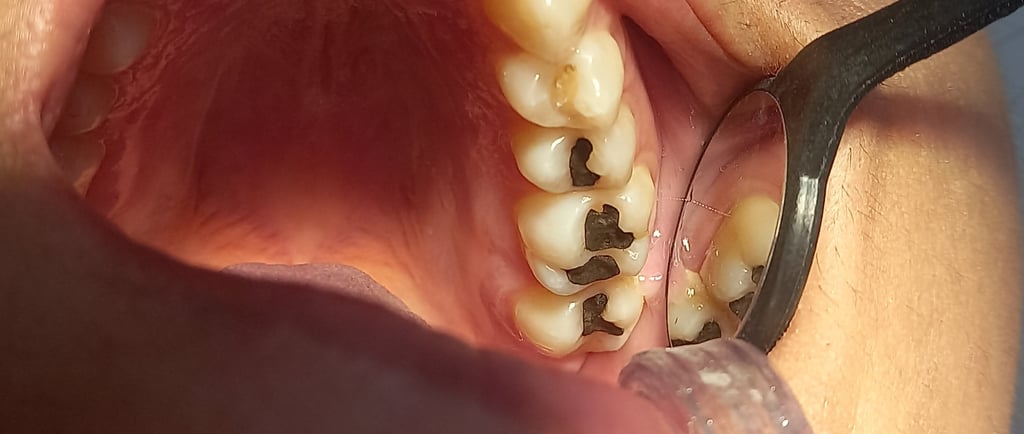

Porque trocar suas amálgamas?

Amálgama possui mercúrio, contração de dilatação diferente e causa micro trincas no esmalte dental consequentemente causando infiltrações.

A amalgama é um material restaurador utilizada na odontologia que contém mercúrio. No entanto, o uso desse material pode trazer alguns efeitos indesejáveis. Devido à sua contração e dilatação diferente em relação ao esmalte dental, isto pode ocasionar micro trincas, essas trincas, por sua vez, podem resultar em infiltrações, permitindo que bactérias e outros agentes nocivos penetrem na estrutura dentária. Esse processo pode levar à deterioração do dente e até mesmo ao surgimento de cáries. Portanto, é importante que os pacientes estejam cientes dos possíveis problemas relacionados ao uso de amalgama e busquem alternativas mais seguras e estéticas para a restauração dental.